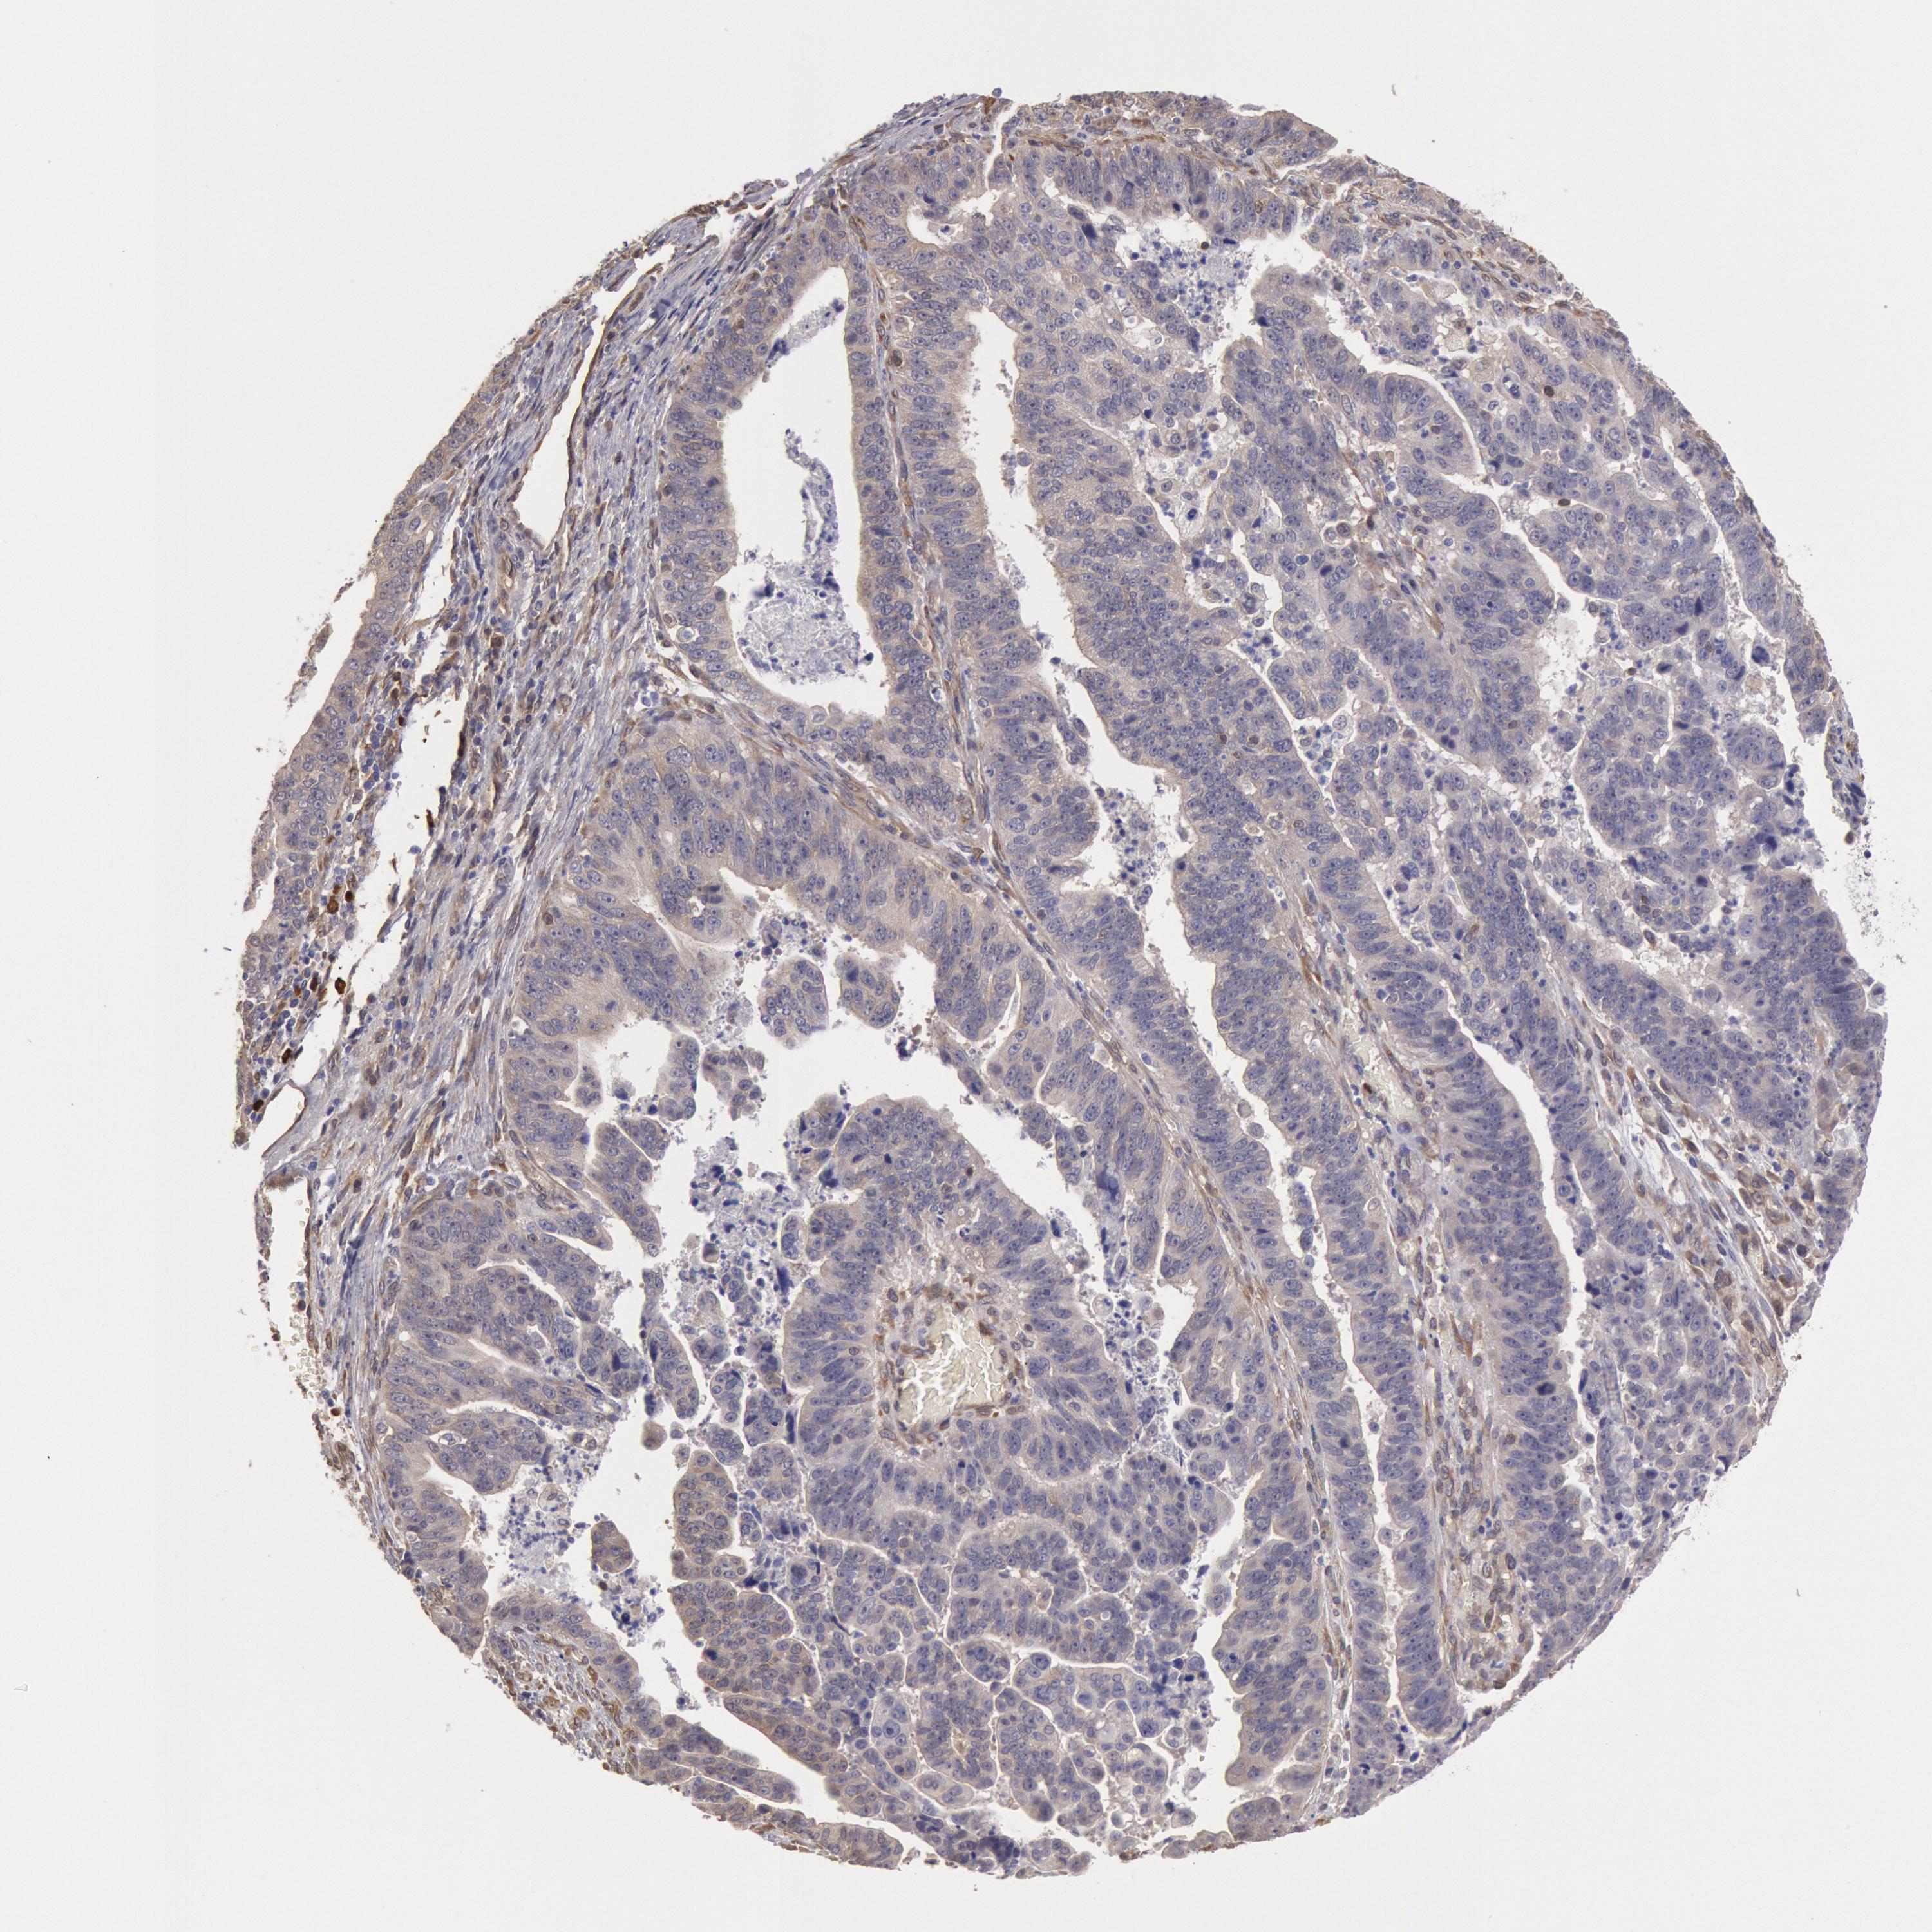

STOMACH CANCER - Protein expressioni

A mouse-over function shows sample information and annotation data. Click on an image to view it in a full screen mode. Samples can be filtered based on level of antibody staining by selecting one or several of the following categories: high, medium, low and not detected. The assay and annotation is described here.

Antibody stainingi

Antibody staining in the annotated cell types in the current human tissue is reported as not detected, low, medium, or high, based on conventional immunohistochemistry profiling in selected tissues. This score is based on the combination of the staining intensity and fraction of stained cells.

Each image is clickable and will lead to virtual microscopy that enables deeper exploration of all samples and also displays staining intensity scores, fraction scores and subcellular localization as well as patient and tissue information for each sample.

Antibody HPA001336

Staining

High

Medium

Low

Not detected

Intensity

Strong

Moderate

Weak

Negative

Quantity

>75%

75%-25%

<25%

None

Location

Nuclear

Cytoplasmic/membranous

Cytoplasmic/membranous,nuclear

Adenocarcinoma, NOS